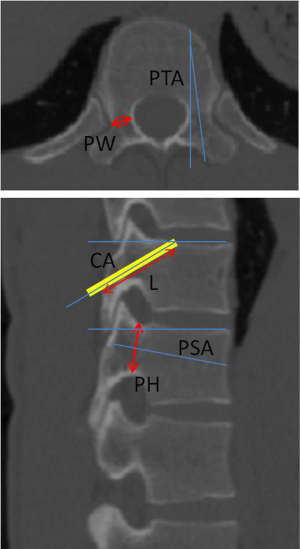

In CT morphometric measurements of T9–T12 region, parameters were measured (Figure 2): (I) pedicle width (PW); (II) pedicle height (PH); (III) pedicle transverse angle (PTA); (IV) pedicle sagittal angle (PSA); (V) length of screw trajectory (L); (VI) cephalad angle (CA). They found that the PW gradually increased from T9 (6.0±1.1 mm) to T12 (9.1±1.6 mm); the PH gradually increased from T9 (13.0±1.3 mm) to T12 (16.8±1.7 mm); while the transverse and sagittal angles of the pedicle tended to decrease gradually from T9 (7.7±1.9° and 14.9±3.4°) to T12 (4.4±1.71° and 10.4±3.1°). The length of trajectory was from 29.7±4.6 mm (T9) to 32.0±2.1 mm (T12), and the CA from 21.4±3.3° (T9) to 27.6±3.9° (T12).